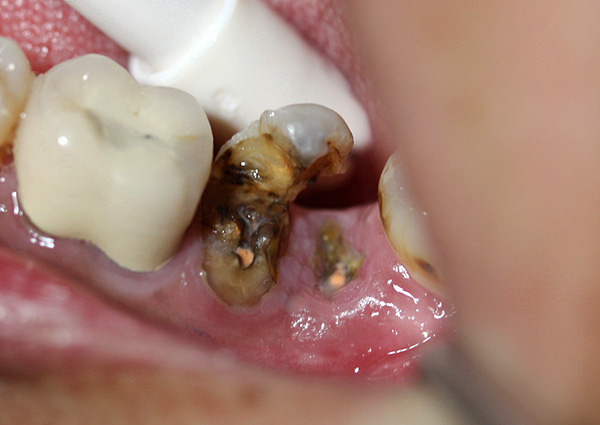

Dal punto di vista di un dentista, la situazione in cui un paziente cammina per anni con un dente cariato, distrutto alla base, appare come segue: questa persona non si dispiace per se stessa. Il fatto è che in questi casi, le radici dei denti devono essere rimosse urgentemente (vedi l'esempio nella foto sotto).

Il motivo è semplice: le radici marce sono un focolaio di infezione e più sono in bocca, più i problemi sono pronunciati e sono tutt'altro che limitati a alitosi costante. Questi "marci" porosi come un aspirapolvere assorbono da soli batteri e particelle di cibo. Oltre al cibo in decomposizione, sui residui dei denti sono presenti anche placca difficile da rimuovere e quasi sempre tartaro sopra e sottogengivale, che causa sofferenza alle gengive.

In quasi il 100% di tali casi, si osserva un processo infiammatorio in cima alle radici marce, accompagnato da rarefazione del tessuto osseo, si forma un granuloma o una cisti. In poche parole, nella parte superiore della radice c'è un sacco purulento, che sta solo aspettando che le ali si spezzino con la formazione di un "flusso".